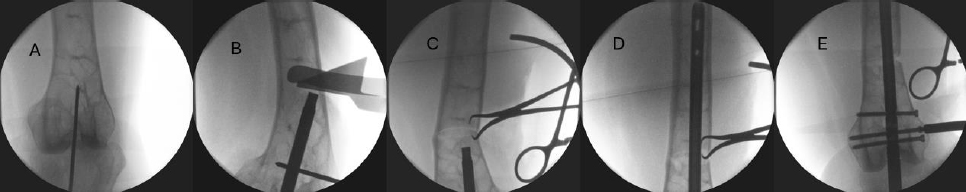

Details regarding surgical technique are supplemented by an example of closing wedge osteotomy of a distal femoral deformity (Fig. 3).

A) Based on preoperative templating, the retrograde starting point is obtained. B) After reaming the entry point to a diameter 1mm larger than the nail diameter, a tubular reduction device is advanced to the apex of the deformity. Osteotomy triangles are used to align the sagittal saw to cut the desired-sized wedge. Circumferential protection of the surrounding soft tissues is achieved with thin, malleable retractors contoured for the specific anatomic site. C) After removal of the wedge, the reduction is obtained and compressed with a pointed reduction clamp placed through unicortical drill holes above and below the osteotomy site. D) The intramedullary nail is advanced across the compressed osteotomy site. E) The intramedullary nail is locked above and below the osteotomy site.